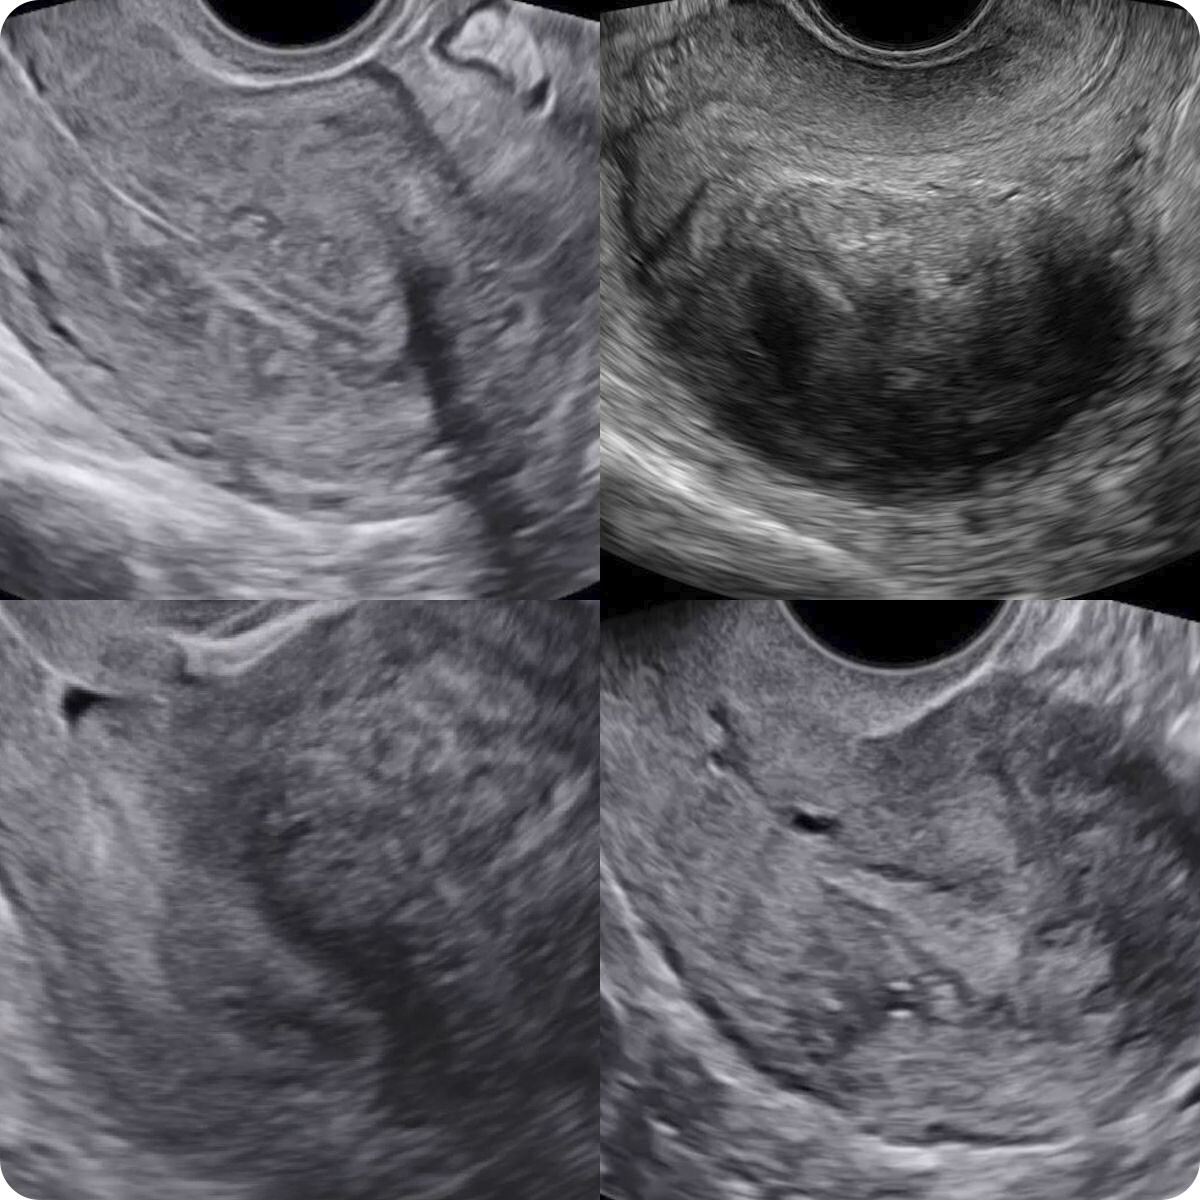

Аденомиоз. Новый пересмотр консенсуса

• MUSA про аденомиоз

• Отличия аденомиоза от миомы

• Аденомиоз. Пересмотр консенсуса (2021)

• Достоверные признаки аденомиоза

• Косвенные признаки аденомиоза

• Примеры. Описания. Заключения